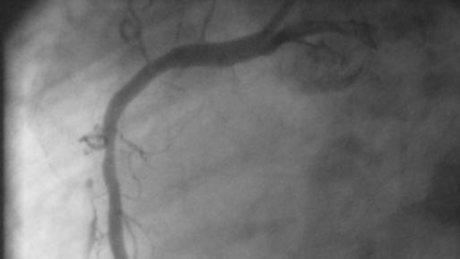

Bild 1: Hochgradige Engstelle nach einem Seitenast der linken Herzkranzarterie.